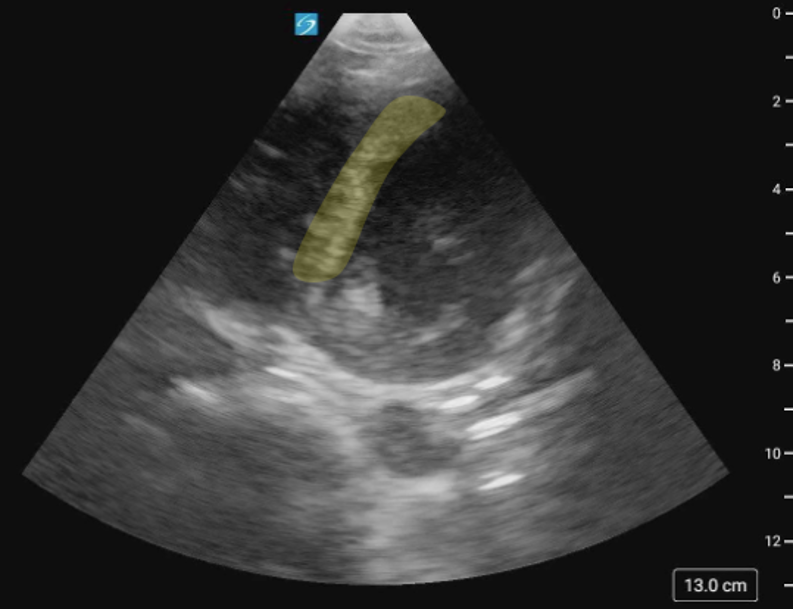

Pitfalls and Limitations

Pitfalls & Limitations

A common limitation when assessing cardiac function is foreshortening of the ventricle, particularly in the PLAX and A4C views (Figure 28,29). Foreshortening occurs when the imaging plane cuts through the heart at an angle that misses the true apex, making the LV appear shorter and more rounded than it actually is. This leads to underestimation of LV size, overestimation of LVfx and poor visualization of true wall motion. To minimize this, adjust your probe position, often one intercostal space lower, if you notice a truncated LV. That said, in some patients, a foreshortened view may be the only achievable window due to body habitus, lung interference, or cooperation. In such cases, it is essential to recognize the limitation and interpret findings with caution. This is why the heart should always be imaged in as many views as possible.

Figure 28: Comparison of PLAX foreshortened VS not foreshortened.

Figure 29: Comparison of A4C foreshortened VS not foreshortened